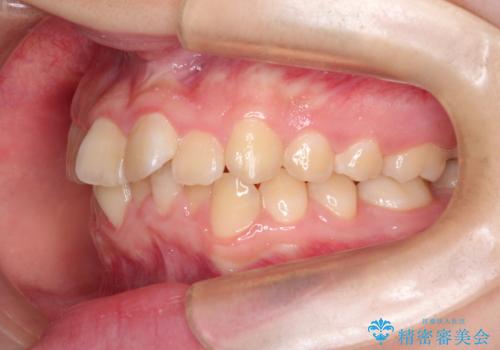

なるべく通院回数を減らして矯正したい インビザラインでのガタガタ矯正

- 上下の歯並びを治したいとのことで来院されました。

受験生ということもあり、なるべく通院回数を減らしての矯正を希望されたので、インビザラインで治療をすることにしました。